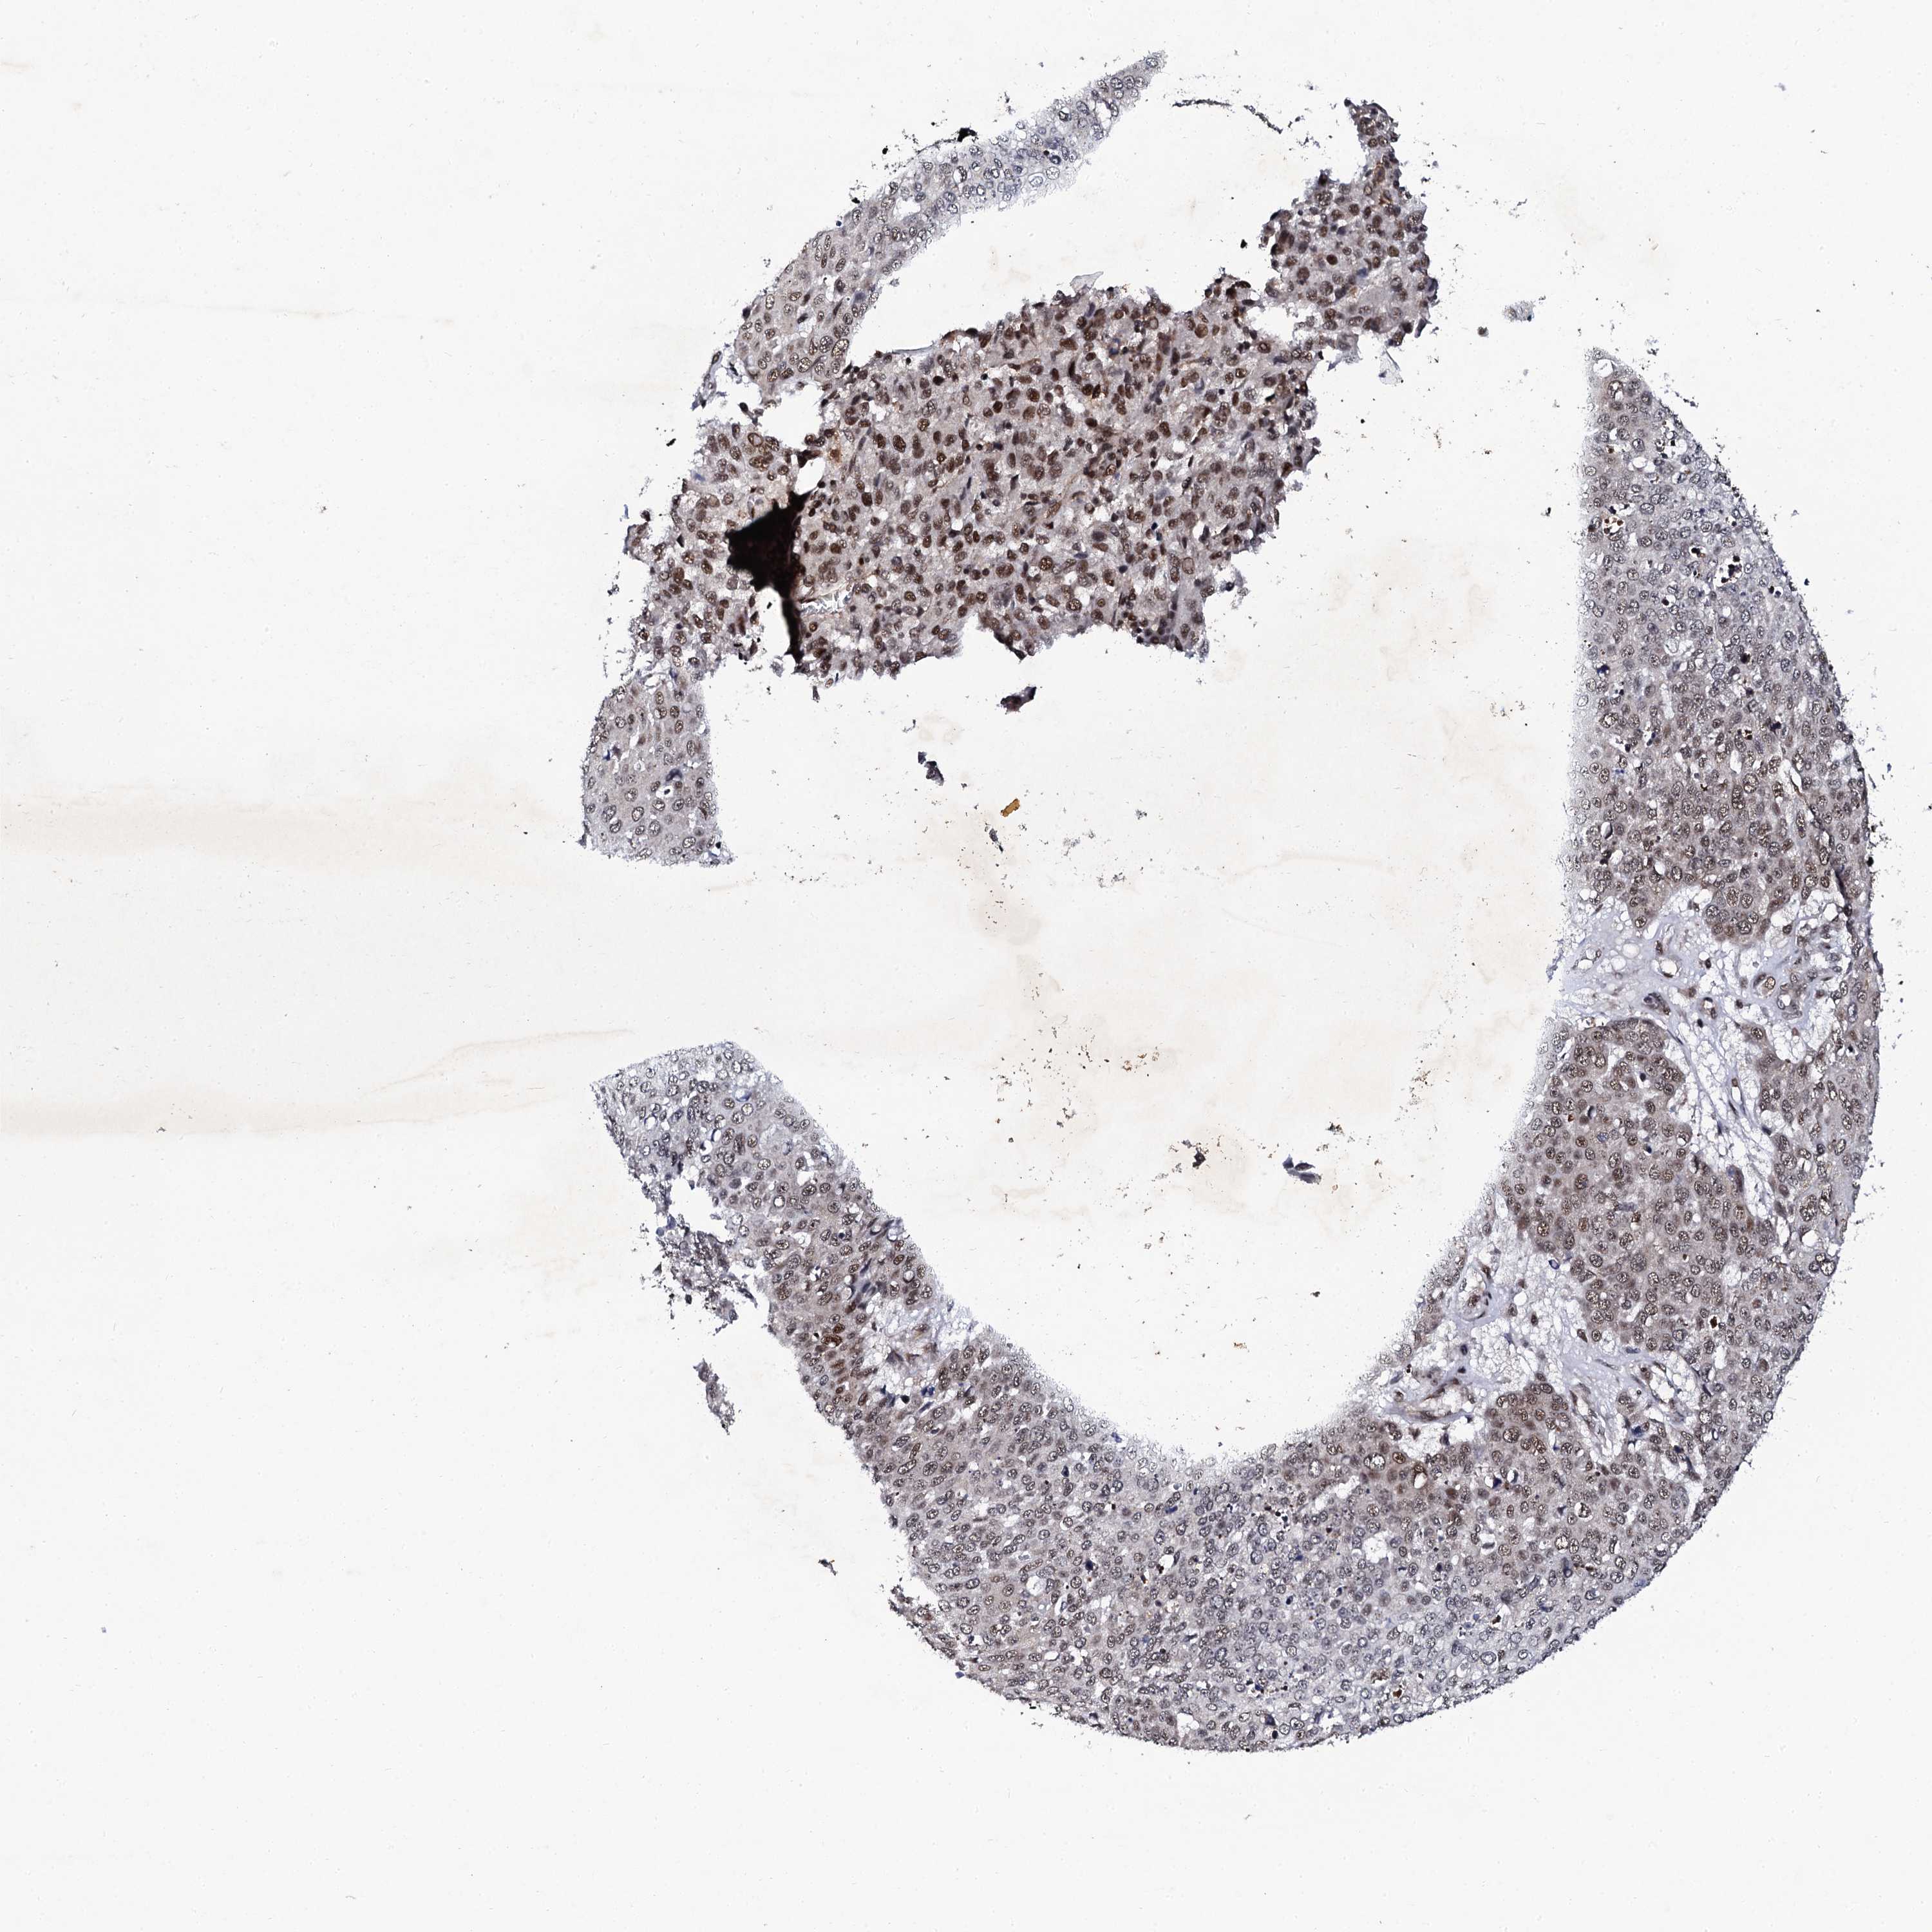

SKIN CANCER - Protein expressioni

A mouse-over function shows sample information and annotation data. Click on an image to view it in a full screen mode. Samples can be filtered based on level of antibody staining by selecting one or several of the following categories: high, medium, low and not detected. The assay and annotation is described here.

Each image is clickable and will lead to virtual microscopy that enables deeper exploration of all samples and also displays staining intensity scores, fraction scores and subcellular localization as well as patient and tissue information for each sample.

Antibody HPA039743

Basal cell carcinoma